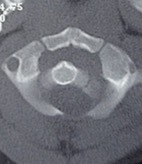

- Figura 2. Tomografia Axial. Inestabilidad Atlanto - Axial